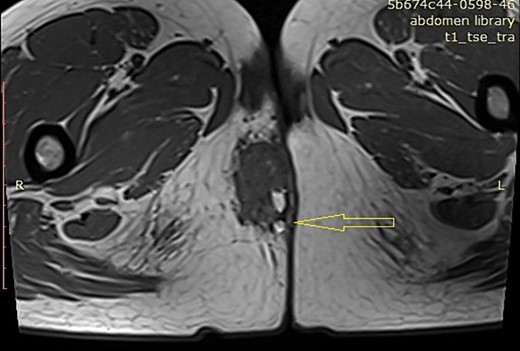

A 33-year-old female patient presented to the emergency department with pain and swelling in the perianal region. The patient was previously treated (a few months ago) for a perianal abscess. MRI revealed a 3.5 × 2 cm mass in the right perianal region pressing on and indenting the right aspect of the distal external sphincter. This mass showed mixed intermediate and high signal intensity. There was an associated diffusion restriction but no avid enhancement after intravenous contrast administration. No fatty components were observed. The exact nature of this mass was indeterminate. (Fig. 3). The patient had two spontaneous parturitions 6 and 3 years precedent, with a placenta defect noted on the second delivery that required manual revision of the uterine cavity.